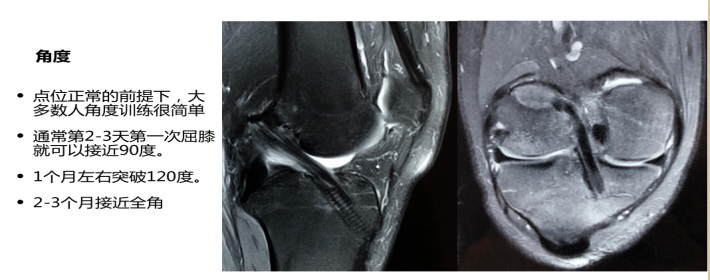

主讲人黄涛2012年毕业于运动人体科学专业,后进入北医三院运动医学科担任康复治疗师,2018年以来先后创建“骨间康复”、“北京葆石康复运动医学诊所”、“Bonespace Smart学院”三家机构,“北京葆石康复运动医学诊所”目前已经发展为北京地区颇有影响力的运动康复机构。黄涛以《前交叉韧带损伤的治疗与康复》为题,结合了大量的临床资料和个人实践经验,用两个小时的时间介绍了前交叉韧带损伤的原因、症状、诊断(查体/影像)、手术、术后康复要点和方案等内容。讲座中展示了他参加临床手术或康复实践中采集的图片和视频材料,如大家熟知的检查前交叉韧带断裂的“抽屉试验”,以及“骨道”建立和韧带重建手术,把书本上刻板、枯燥、晦涩的知识,生动直观的展现在学生眼前。他用幽默的语言和丰富的案例积极与学生交流互动,并以自己在校学习和工作经历激励大家主动加强学习,在打好专业基础、拓展医疗知识、勤于动手等方面提升自身能力。